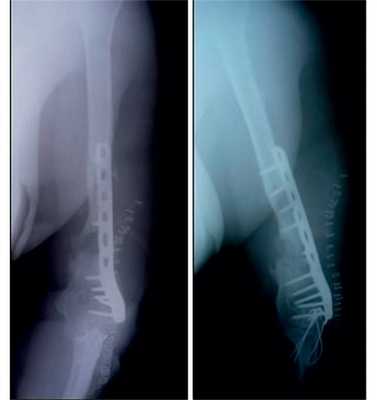

Рис. 5. Пациентка И. Этапное оперативное вмешательство. а — замещение дефекта плечевой кости цементным спейсером; б — транспозиция торакодорсального лоскута в область мягкотканного дефекта плеча; в — послеоперационная рентгенограмма.

Рис. 6. Рентгенограммы пациентки И. после удаления цементного спейсера.

Рис. 7. Оперативное лечение пациентки И.: пластика левой плечевой кости свободным кровоснабжаемым трансплантатом из малоберцовой кости.

На рис. 10-14 Рис. 10. Рентгенограмма пациентки Н. до операции. Рис. 14. Внешний вид и функция пациентки Н. через 8 мес после операции. представлены этапы обследования и лечения пациентки Н.

Рис. 11. Пациентка Н. Оперативное лечение: резекция зоны ложного сустава левой плечевой кости, остеосинтез пластиной и винтами. Пластика свободным кровоснабжаемым трансплантатом из внутреннего мыщелка бедренной кости.

Рис. 12. Рентгенограммы пациентки Н. после операции.

Рис. 13. Рентгенограммы пациентки Н. через 8 мес после операции.